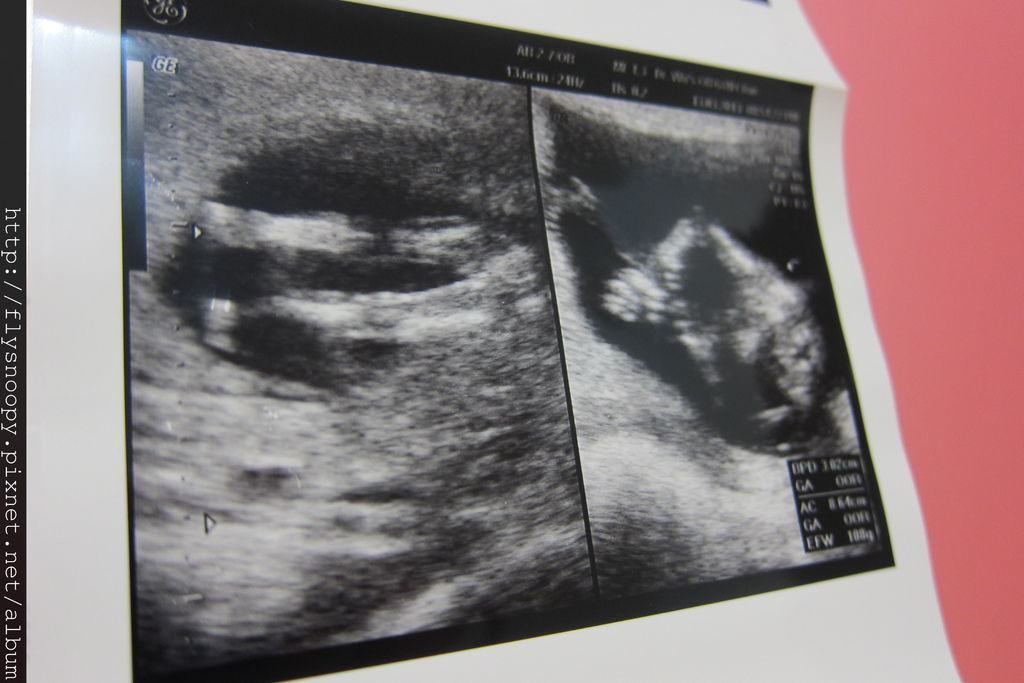

上面三張超音波照片就是這次急診時拍的

這次baby CRL 是7.01,生長一切正常,但是我還是很擔心

醫生說流血就是有流產跡象,所以開藥並要我在家臥床安胎